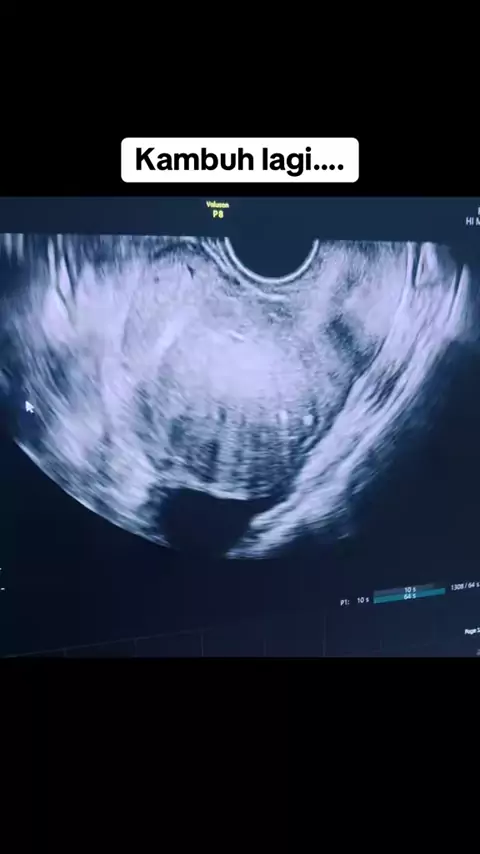

Kambuh lagi seperti biasanya.. Penanganan Endometriosis harus jangka panjang.. ini penyakit kronis dan bisa berlangsung seumur hidup.. @klinikdesani